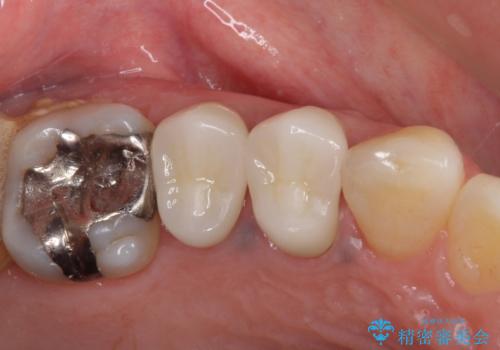

オールセラミッククラウン 咬むと痛む奥歯の治療